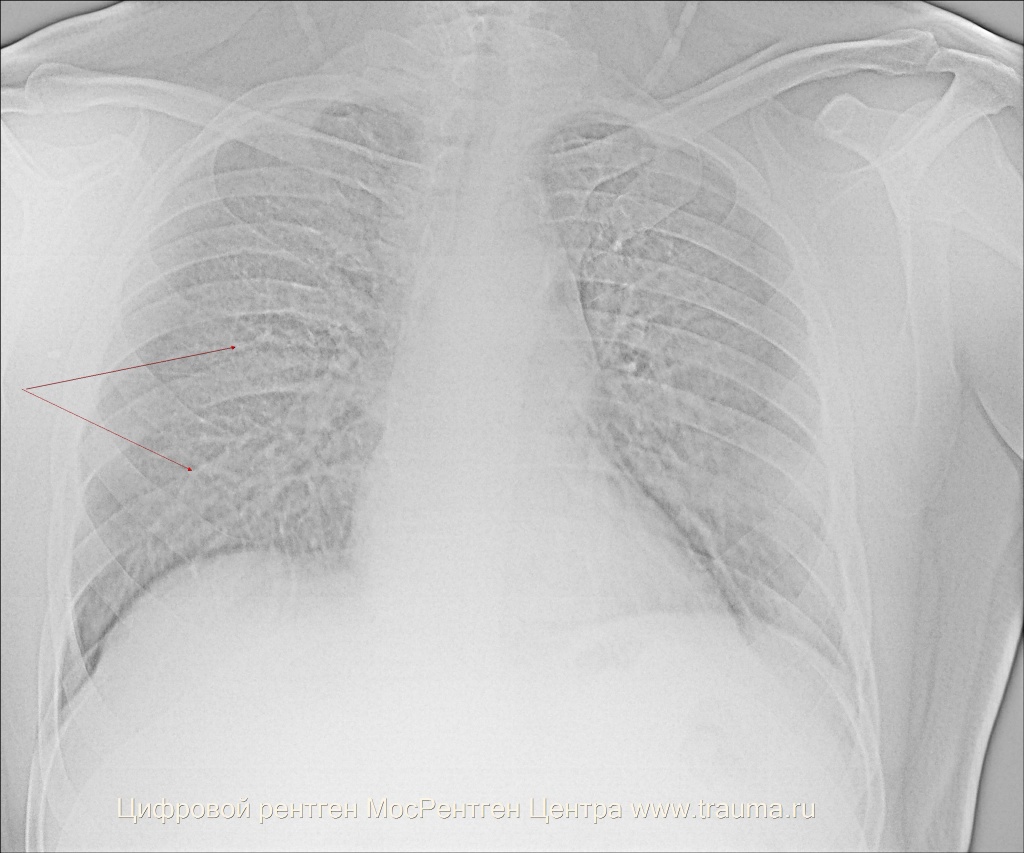

Традиционная двухпроекционная рентгенография и продольная томография регистрируют далеко зашедшие случаи бронхиолитов, выявляя диффузное, диффузноочаговое усиление легочного рисунка, эмфизематозно вздутые участки легкого, перибронхиальный фиброз крупных бронхов, уплотнение корней, малую подвижность диафрагмы (рис. 1).

Изменения на рентгенограммах неспецифичны и наблюдаются не только при бронхиолитах, но и в целом ряде других патологических состояний.